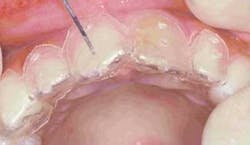

Once optimal gingival contours were achieved, preparation of the teeth continued. Incisal reduction was achieved using the coarse football diamond (Figure 11) to create a butt joint. The preparations were smoothed using the superfine tapered diamond (836V-1) (Figure 12). Adequate reduction was verified using the thin transparent Preparation Guide, made from the image-inspired wax-up. By checking all surfaces with the periodontal probe through the appropriate holes in the seated preparation splint (Figure 13), you can substantially enhance your success with porcelain restorations of adequate thickness and resistance. Finally, all sharp line angles were smoothed using the Shofu snap-on discs (Figure 14), further increasing resistance and strength. When the preparations were complete, an Impregum Soft polyether impression was taken (Figure 15).